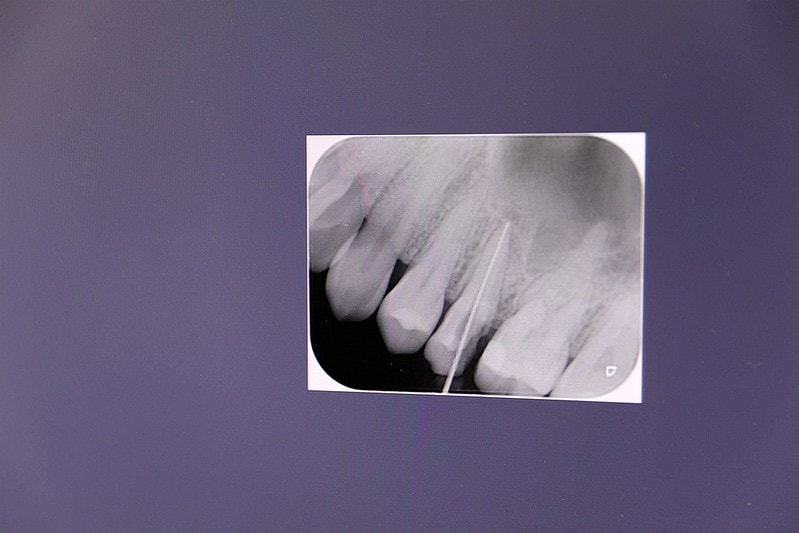

接著就是幫牙齒拍全口的X光片

才能知道每顆牙齒目前的狀況

幫牙齒照完X光片後

這次幫羽諾治療的牙齒何家銘院長還會很仔細地抽出時間為羽諾說明牙齒的狀況

羽諾這次治療的共有兩顆牙齒 一顆牙齒是確定要根管治療了 必須抽神經

另一顆牙齒則可以保留神經 但由於這顆牙齒已經有點裂掉產生缺口了

所以也是必須在治療完畢後 放入柱心及牙冠

首先先將牙根清潔完畢後 照牙根的X光

經過X光片後得以測量牙根的長度 能更確定清潔牙根的程度

清牙根的時間長短就是看牙根受感的程度來判段

羽諾大概一顆牙齒需要來到兩次 才可以將牙根清潔完畢